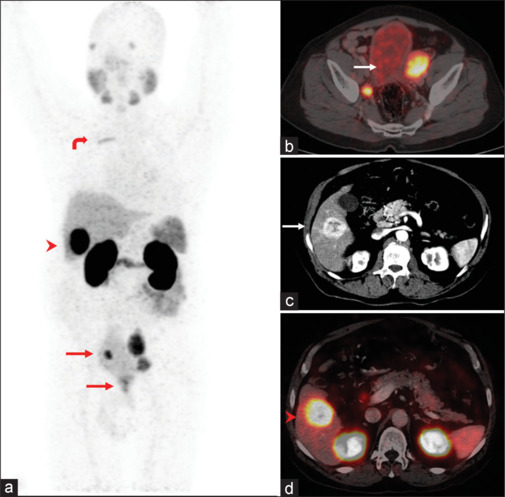

Isolated liver metastasis from prostate cancer is exceedingly rare. Prostate-specific membrane antigen-positron emission tomography/computed tomography has become the one-stop shop imaging in prostate cancer, but the uptake is a relatively nonspecific tracer and its expression can be seen in a plethora of nonprostatic solid tumors. We report one such example of an oligometastatic prostate cancer who presented with an isolated liver lesion which turned out to be an incidental hepatocellular carcinoma, thus representing a potentially unique diagnostic challenge.